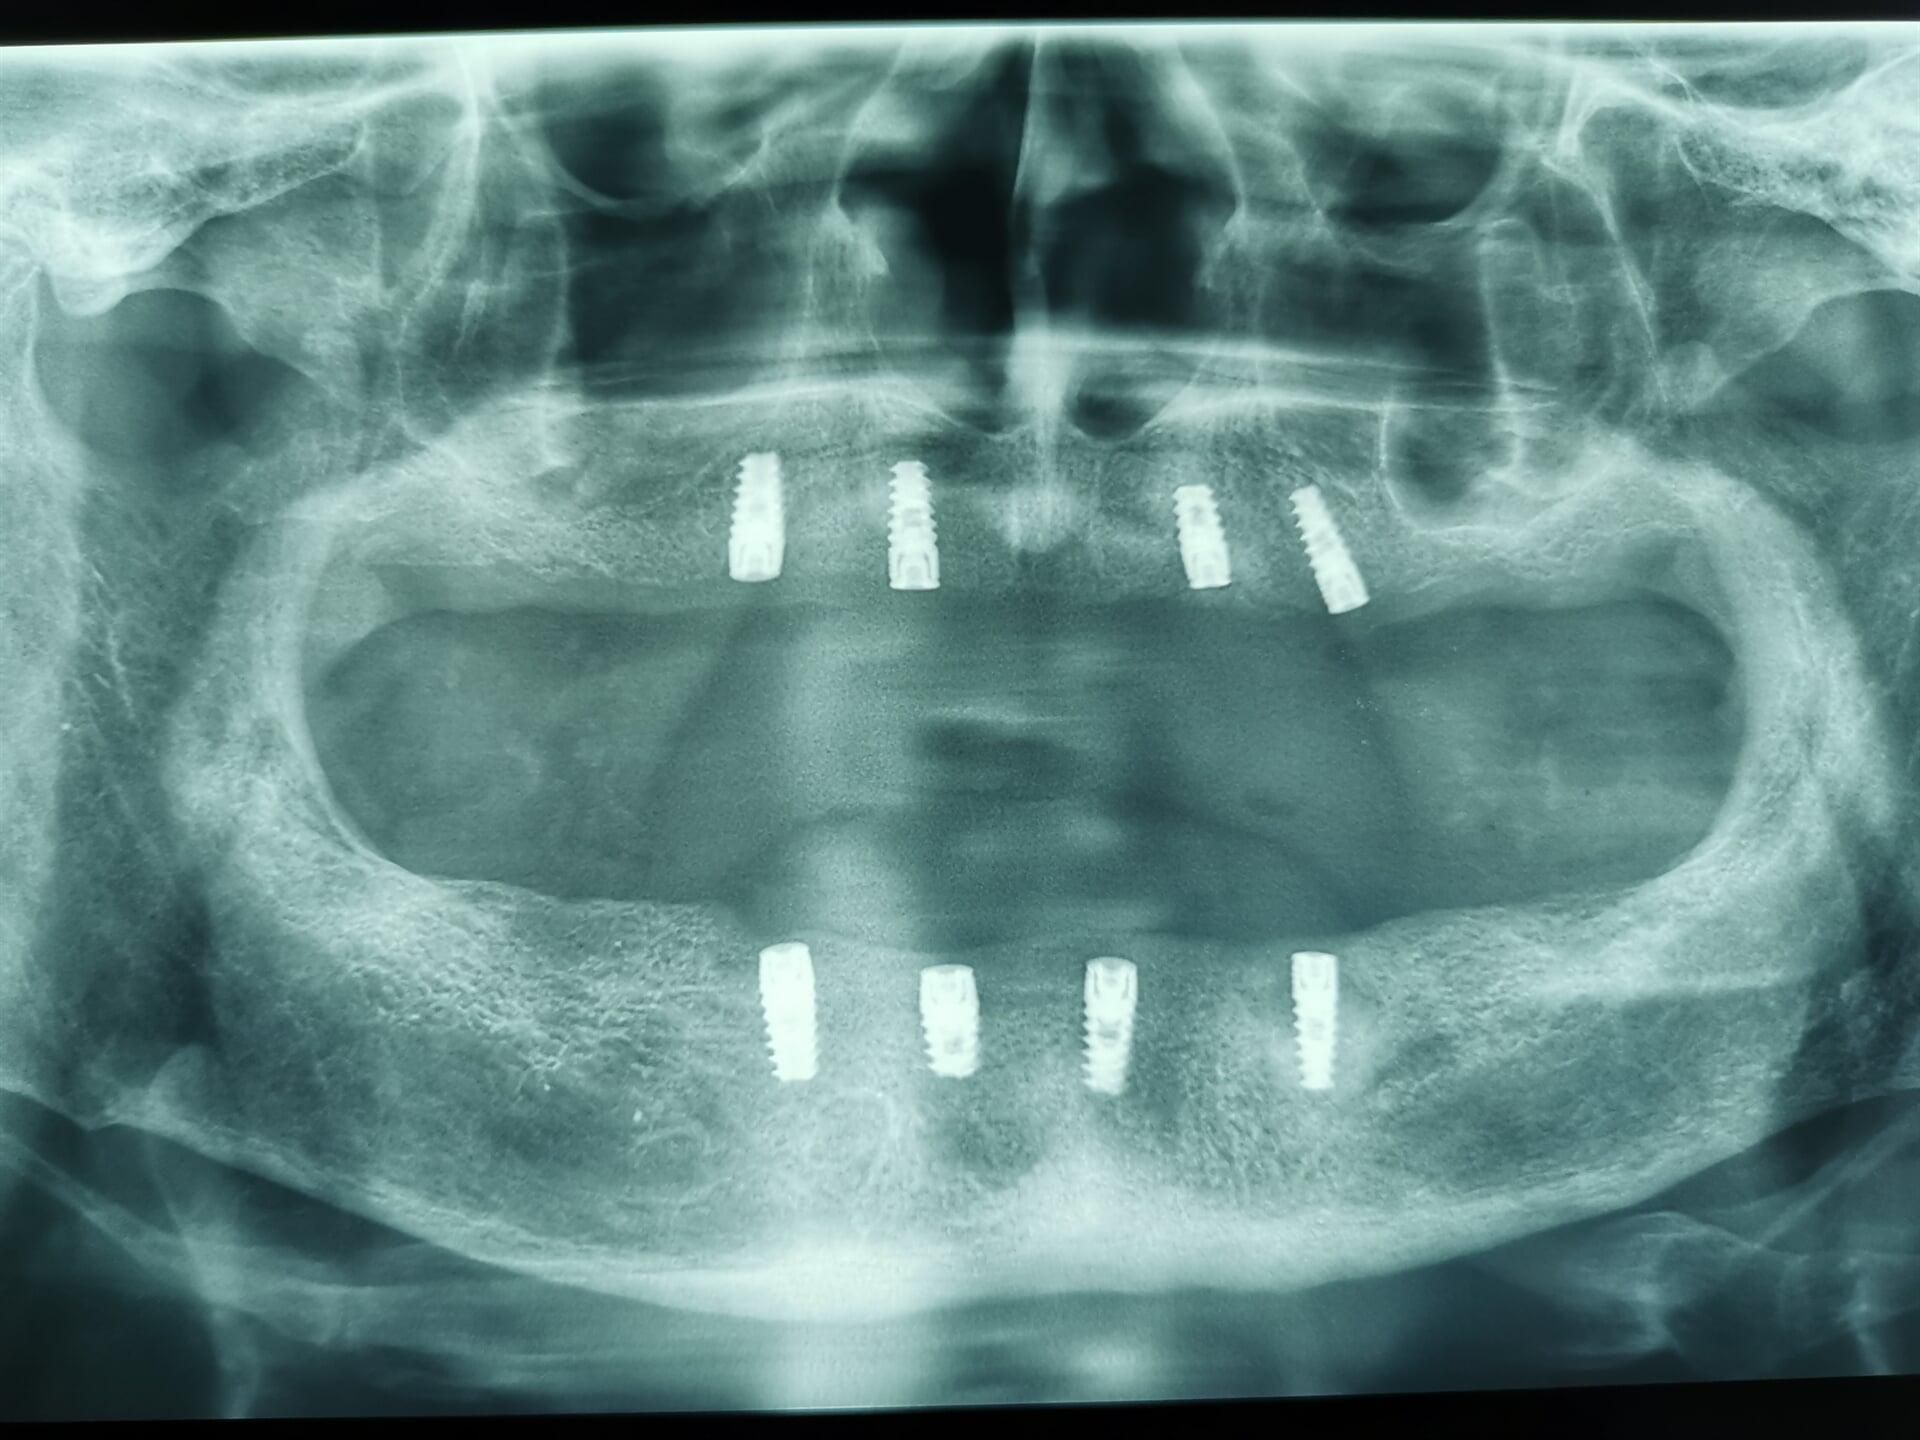

IMPLANTES

DENTALES

Antes de pensar en colocar un implante, primero deberemos realizarte una serie de estudios, así como valoración a detalle de tu cavidad oral para proponer que tratamiento es el ideal para ti.

En CIMOH contamos con equipo multidisciplinario para lograr evaluarte y decidir si eres o no candidato para este tipo de tratamientos, en caso de no serlo, también de sugeriremos diferentes opciones para tu rehabilitación.